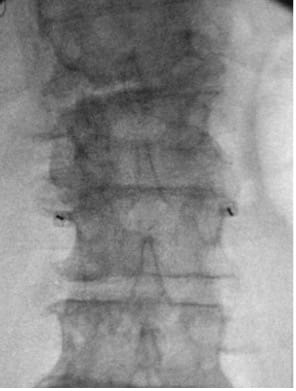

- Obtain PA view centered at L3, visualizing L2 and L4.

- Place marker 22G or 25G spinal needles bilaterally at L3 TP–SAP junction; confirm tip at superior TP border on the lateral view.

| Fluoroscopic Views | |

| True Poster-Anterior (PA) View |

|